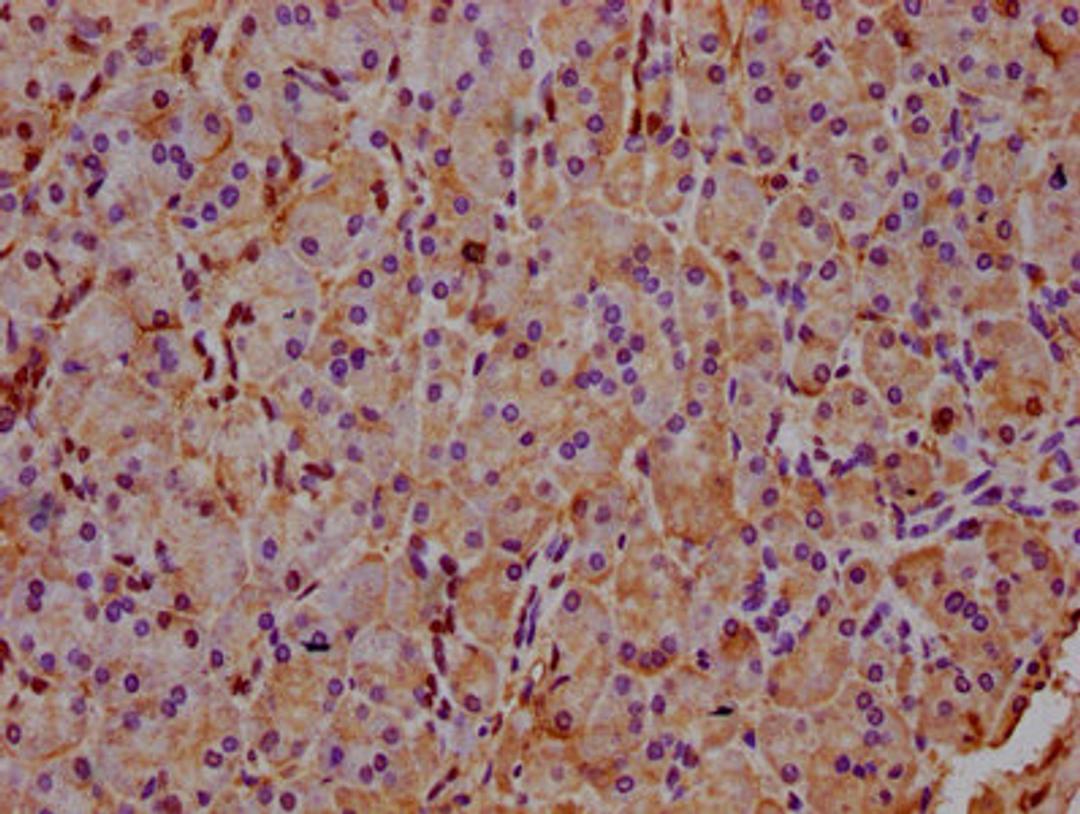

IHC image of CSB-PA873641LA01HU diluted at 1:400 and staining in paraffin-embedded human pancreatic tissue performed on a Leica BondTM system. After dewaxing and hydration, antigen retrieval was mediated by high pressure in a citrate buffer (pH 6.0). Section was blocked with 10% normal goat serum 30min at RT. Then primary antibody (1% BSA) was incubated at 4°C overnight. The primary is detected by a biotinylated secondary antibody and visualized using an HRP conjugated SP system.